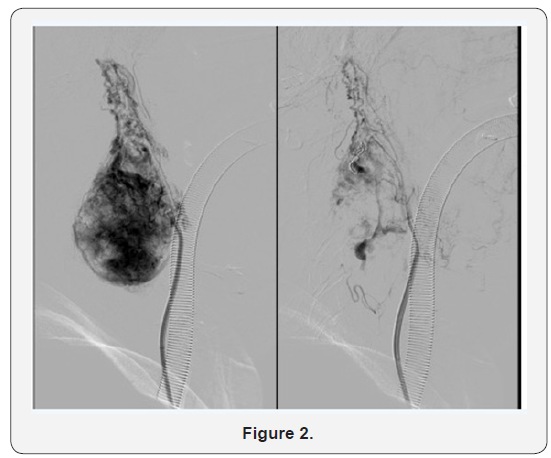

48 hours prior to surgical resection, transfemoral approach embolization of more than 80 % of the vascularisation was performed with polyvinyl alcohol (PVA) particles and coils (Figure 2). Surgical resection was programmed the day after embolization (Figure 3). After surgery the patient presented isolated episodes of nausea and dysphonia until discharge from the hospital. One year after the procedure dysphonia remained as a residual symptom due to partial vocal cord paralisys, probably due to recurrent laringueal nerve damage during resection, but no tumour recurrence was found.

Embolization prior to surgical resection reduces tumoural size and vascularisation and makes excision easier with less blood loss. It should be performed 48 hours before surgery in order to avoid local inflammatory changes that could make resection difficult. This technique, can be beneficious prior to surgery. Complications such as distal embolization, necrosis or stroke may occur as a consequence of this procedure. In order to determine the arterial supply and the extent of tumour vascularity, selective angiographic injections of the internal and external carotid arteries are performed. Carotid body PGs are successfully embolized through transfemoral transarterial access. Direct puncture of embolizing materials has been described. This technique has the inconvenient of important complications such as migration of the material into intracranial circulation. Some authors have reported the use of balloons to protect intracranial circulation while performing tumour embolization [9-11].